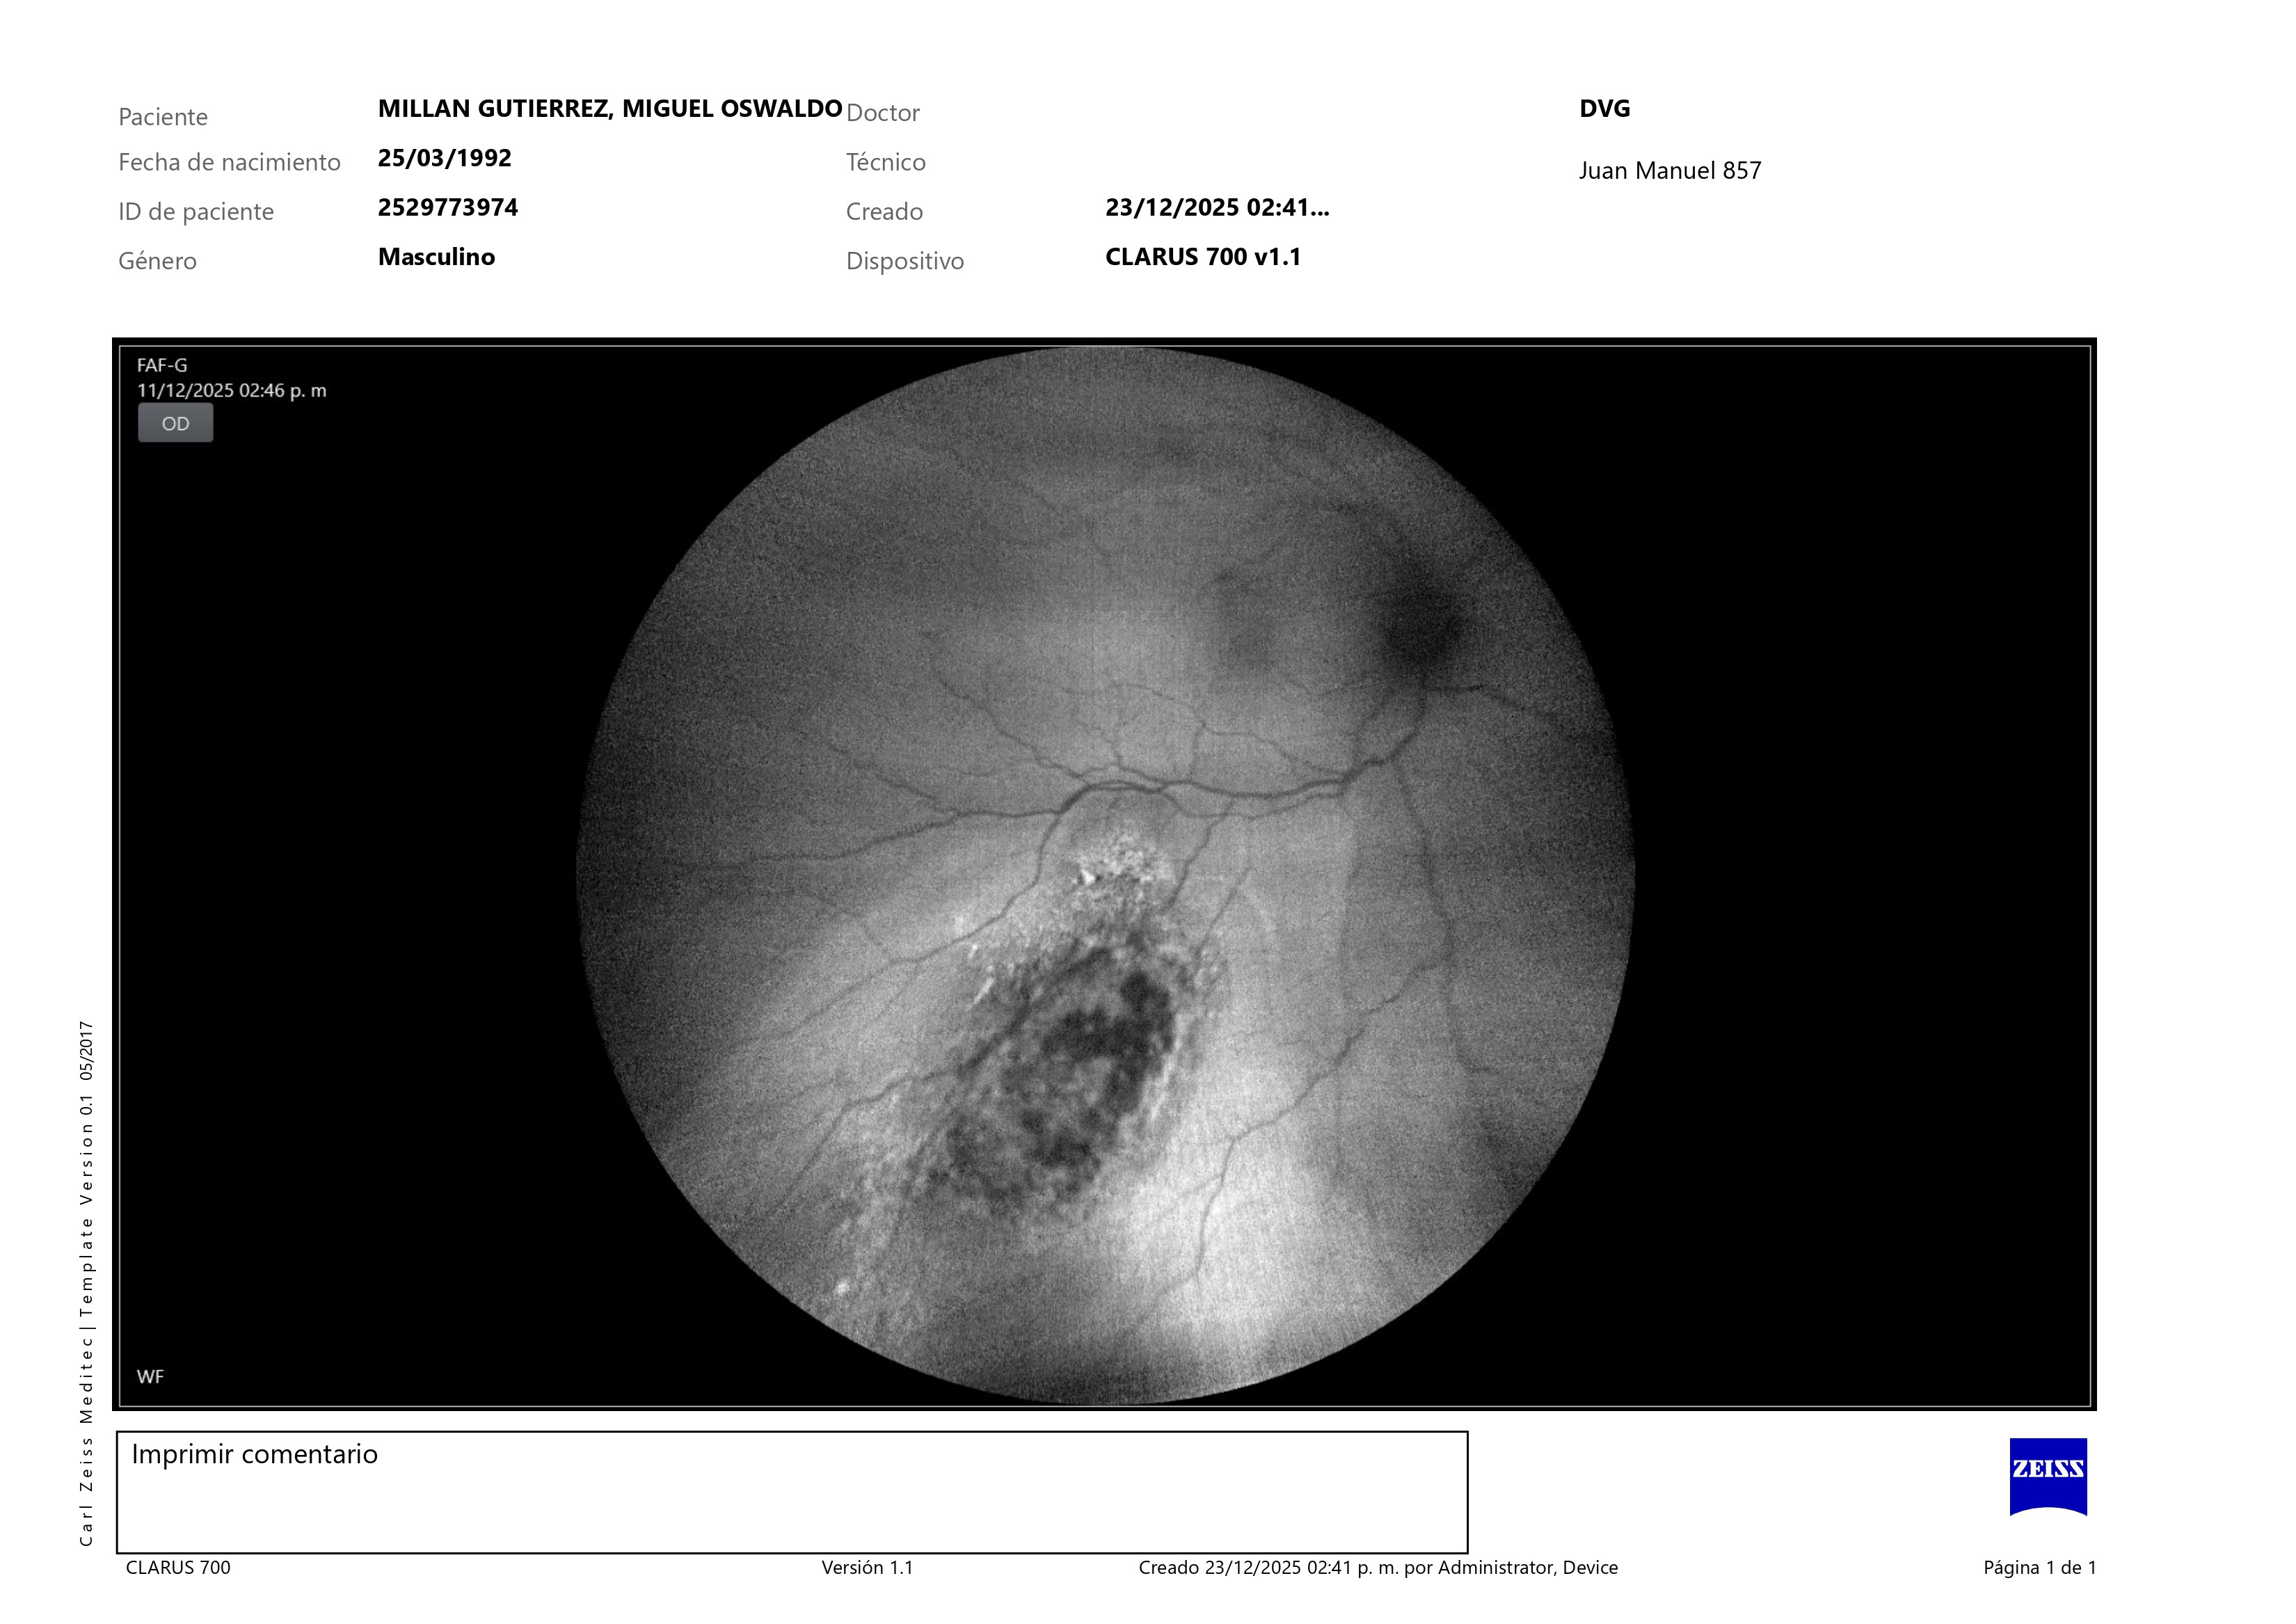

El 11 de diciembre fui diagnosticado con melanoma coroideo, un tipo de cáncer ocular poco común que crece debajo de la retina. En mi caso, el tumor ya provocó un desprendimiento de retina y, si no se trata a tiempo, puede extenderse a órganos como el hígado o los pulmones.

On December 11th, I was diagnosed with choroidal melanoma, a rare type of eye cancer that grows beneath the retina. In my case, the tumor has already caused a retinal detachment and, if not treated in time, it can spread to organs such as my liver or lungs.